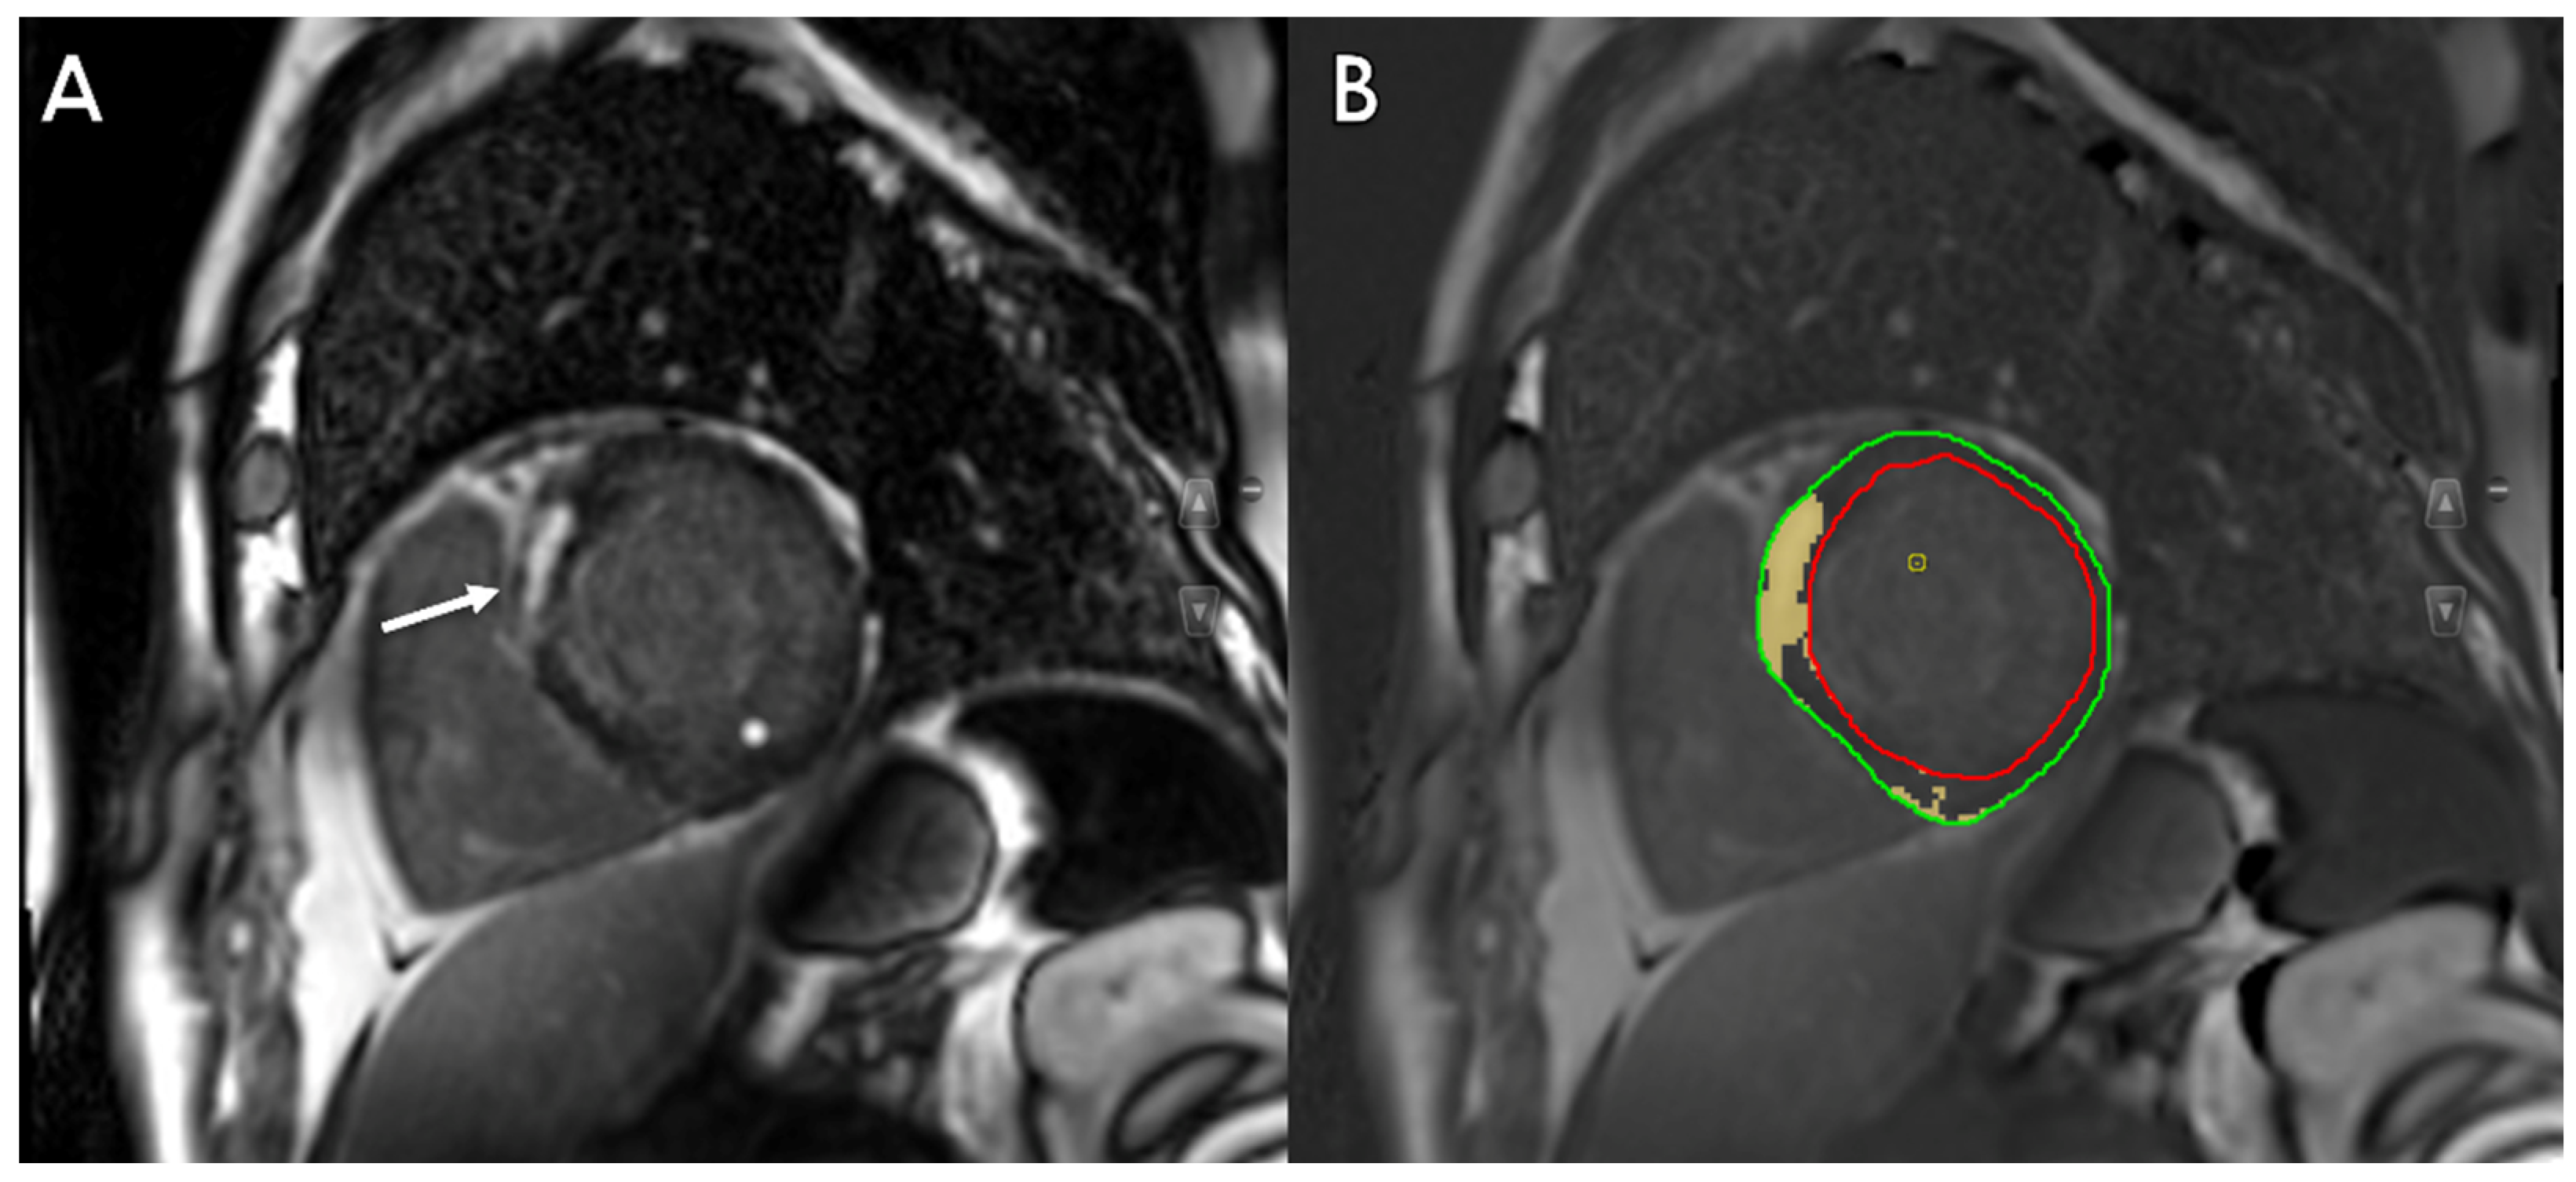

- Moccia, S.; Banali, R.; Martini, C.; Muscogiuri, G.; Pontone, G.; Pepi, M.; Caiani, E.G. Development and testing of a deep learning-based strategy for scar segmentation on CMR-LGE images. MAGMA 2019, 32, 187–195. [Google Scholar] [CrossRef]

- Zabihollahy, F.; Rajchl, M.; White, J.A.; Ukwatta, E. Fully automated segmentation of left ventricular scar from 3D late gadolinium enhancement magnetic resonance imaging using a cascaded multi-planar U-Net (CMPU-Net). Med. Phys. 2020, 47, 1645–1655. [Google Scholar] [CrossRef]

- Zhang, N.; Yang, G.; Gao, Z.; Xu, C.; Zhang, Y.; Shi, R.; Keegan, J.; Xu, L.; Zhang, H.; Fan, Z.; et al. Deep Learning for Diagnosis of Chronic Myocardial Infarction on Nonenhanced Cardiac Cine MRI. Radiology 2019, 291, 606–617. [Google Scholar] [CrossRef]

- Zhang, Q.; Burrage, M.K.; Shanmuganathan, M.; Gonzales, R.A.; Lukaschuk, E.; Thomas, K.E.; Mills, R.; Leal Pelado, J.; Nikolaidou, C.; Popescu, I.A.; et al. Artificial Intelligence for Contrast-Free MRI: Scar Assessment in Myocardial Infarction Using Deep Learning-Based Virtual Native Enhancement. Circulation 2022, 146, 1492–1503. [Google Scholar] [CrossRef]

- Leiner, T. Deep Learning for Detection of Myocardial Scar Tissue: Goodbye to Gadolinium? Radiology 2019, 291, 618–619. [Google Scholar] [CrossRef]

- Sendra-Balcells, C.; Campello, V.M.; Martin-Isla, C.; Vilades, D.; Descalzo, M.L.; Guala, A.; Rodriguez-Palomares, J.F.; Lekadir, K. Domain generalization in deep learning for contrast-enhanced imaging. Comput. Biol. Med. 2022, 149, 106052. [Google Scholar] [CrossRef]